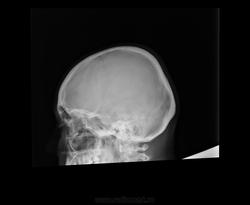

Помогите, пожалуйста, с описанием снимка черепа https://radiomed.ru/sites/default/files/styles/case_slider_image/public/user/19361/ffe4984c7ada4fa089e1ecdd63211bcf_1.jpg?itok=ycAIFYVP ID:46704 Mon, 21/04/2014 - 12:41 #1 Nela Offline Last seen: 6 years 4 months ago Joined: 12.05.2009 - 20:43 Posts: 1847 Норма Mon, 21/04/2014 - 18:44 #2 largooowinch Offline Last seen: 10 years 3 months ago Joined: 29.10.2013 - 22:07 Posts: 65 я за норму Mon, 21/04/2014 - 21:46 #3 Дмитрий Волегов Offline Last seen: 3 years 9 months ago Joined: 22.05.2013 - 00:32 Posts: 1148 Турецкого седла мне не видно. Предложил бы переснять. С Уважением, Дмитрий. Mon, 21/04/2014 - 23:46 #4 OPEXOB Offline Last seen: 10 years 2 months ago Joined: 26.07.2008 - 10:02 Posts: 280 Ужасная укладка - лаборанту по рукам линейкой ! Wed, 30/04/2014 - 10:55 #5 Доктор Ре. Offline Last seen: 10 years 5 months ago Joined: 15.04.2014 - 16:37 Posts: 129 На мой взгляд имеется некоторое уплощение в переднезаднем направлении и форма черепа по типу конической. Может ли здесь быть акроцефалия?

Турецкого седла мне не видно. Предложил бы переснять.

С Уважением, Дмитрий.

Ужасная укладка - лаборанту по рукам линейкой !

На мой взгляд имеется некоторое уплощение в переднезаднем направлении и форма черепа по типу конической. Может ли здесь быть акроцефалия?